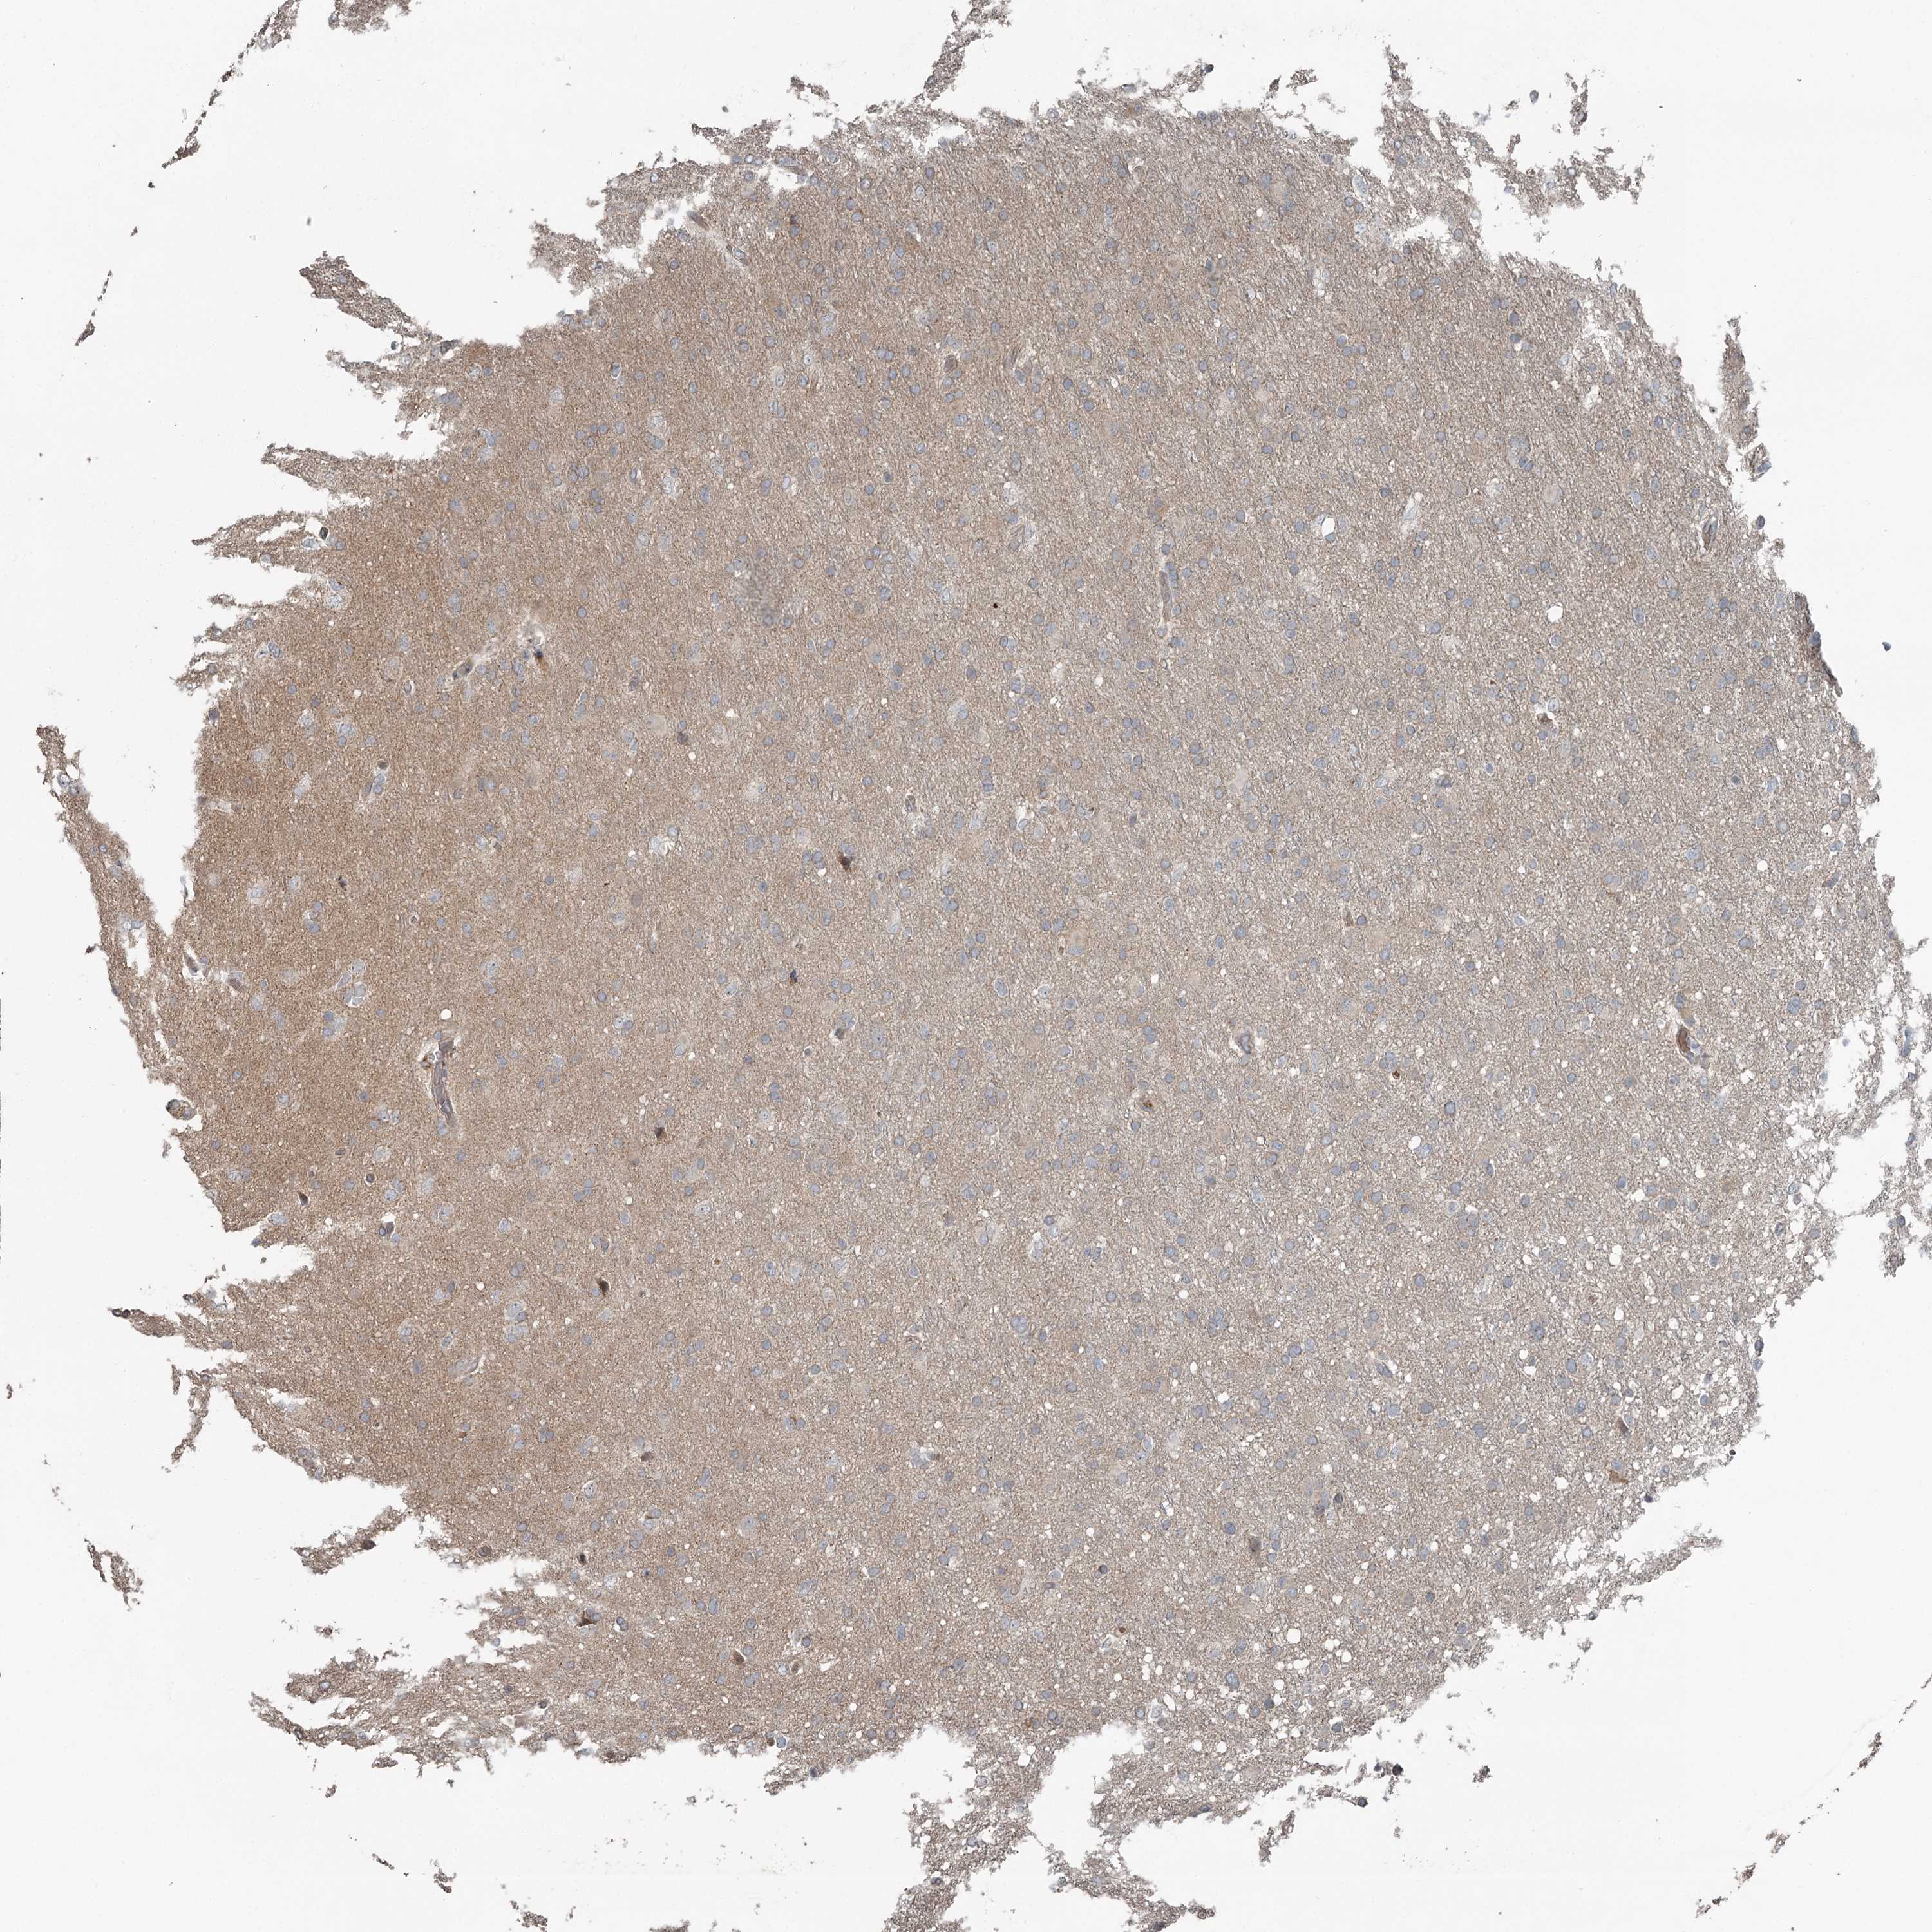

GLIOMA - Protein expressioni

A mouse-over function shows sample information and annotation data. Click on an image to view it in a full screen mode. Samples can be filtered based on level of antibody staining by selecting one or several of the following categories: high, medium, low and not detected. The assay and annotation is described here.

Note that samples used for immunohistochemistry by the Human Protein Atlas do not correspond to samples in the TCGA dataset.

Antibody stainingi

Antibody staining in the annotated cell types in the current human tissue is reported as not detected, low, medium, or high, based on conventional immunohistochemistry profiling in selected tissues. This score is based on the combination of the staining intensity and fraction of stained cells.

Each image is clickable and will lead to virtual microscopy that enables deeper exploration of all samples and also displays staining intensity scores, fraction scores and subcellular localization as well as patient and tissue information for each sample.

Antibody HPA038163

Antibody HPA038164

Staining

High

Medium

Low

Not detected

Intensity

Strong

Moderate

Weak

Negative

Quantity

>75%

75%-25%

<25%

None

Location

Nuclear

Cytoplasmic/membranous

Cytoplasmic/membranous,nuclear

Glioma, malignant, High grade

Glioma, malignant, Low grade

Glioblastoma, NOS